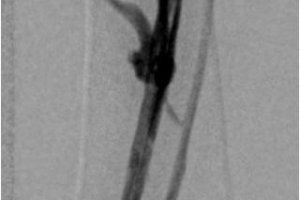

Посттромбофлебитическая болезнь (ПТФБ) развивается у 40-60 % пациентов после перенесенного тромбоза глубоких вен. ПТФБ является одной из разновидностей хронических заболеваний вен нижних конечностей и приводит к трофическим нарушениям. В центре сосудистой хирургии им. Т.Топпера активно занимаются реконструктивной хирургией вен. В настоящее время накоплен большей опыт лечения пациентов с посттромбофлебитической болезнью. Прежде всего это баллонная ангиопластика вен, которая по необходимости может быть дополнена стентированием. На базе нашей клиники вы можете пройти комплексное обследование вен и получить квалифицированную помощь.